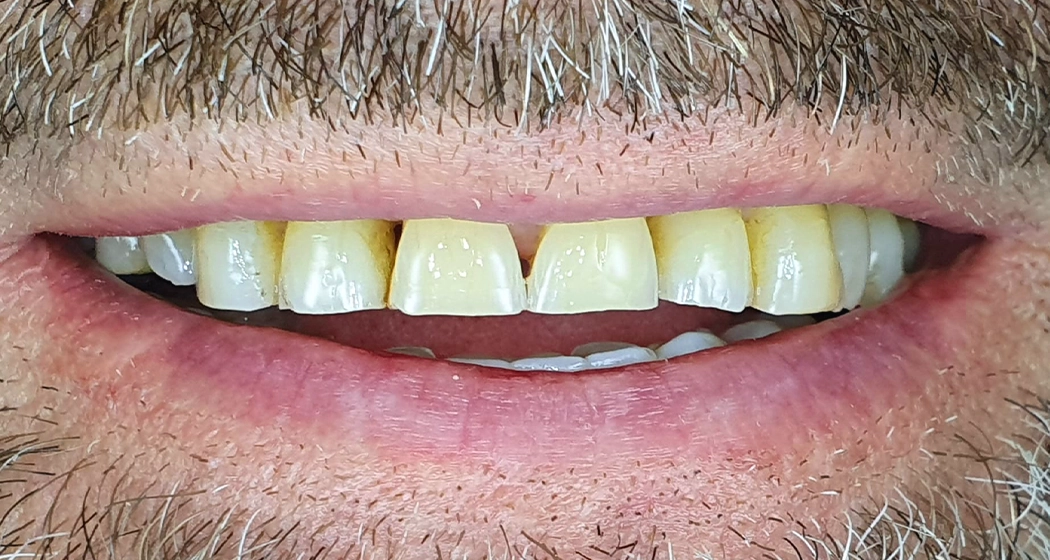

Casos clínicos de Estética Dentária

Casos clínicos de estética dentária que refletem a harmonia, a naturalidade e a estética do sorriso.